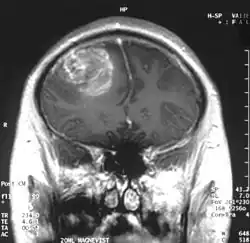

Мультиформная глиобласто́ма (англ. Glioblastoma multiforme, GBM) — наиболее частая и наиболее агрессивная форма опухоли мозга, которая составляет до 52 % первичных опухолей мозга и до 20 % всех внутричерепных опухолей. Несмотря на то, что глиобластома является наиболее частой первичной опухолью мозга, на 100 000 жителей Европы и Северной Америки регистрируется всего 2—3 случая заболевания[1]. Термин «глиобластома» подразумевает два варианта этой болезни: гигантоклеточная глиобластома и глиосаркома.